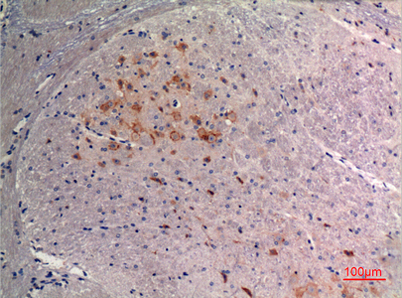

Product name: FGF-9 rabbit pAb

Dilutions: Western Blot: 1/500 - 1/2000. IHC-p: 1:100-300 ELISA: 1/20000. Not yet tested in other applications.

Immunogen: The antiserum was produced against synthesized peptide derived from the C-terminal region of human FGF9. AA range:141-190